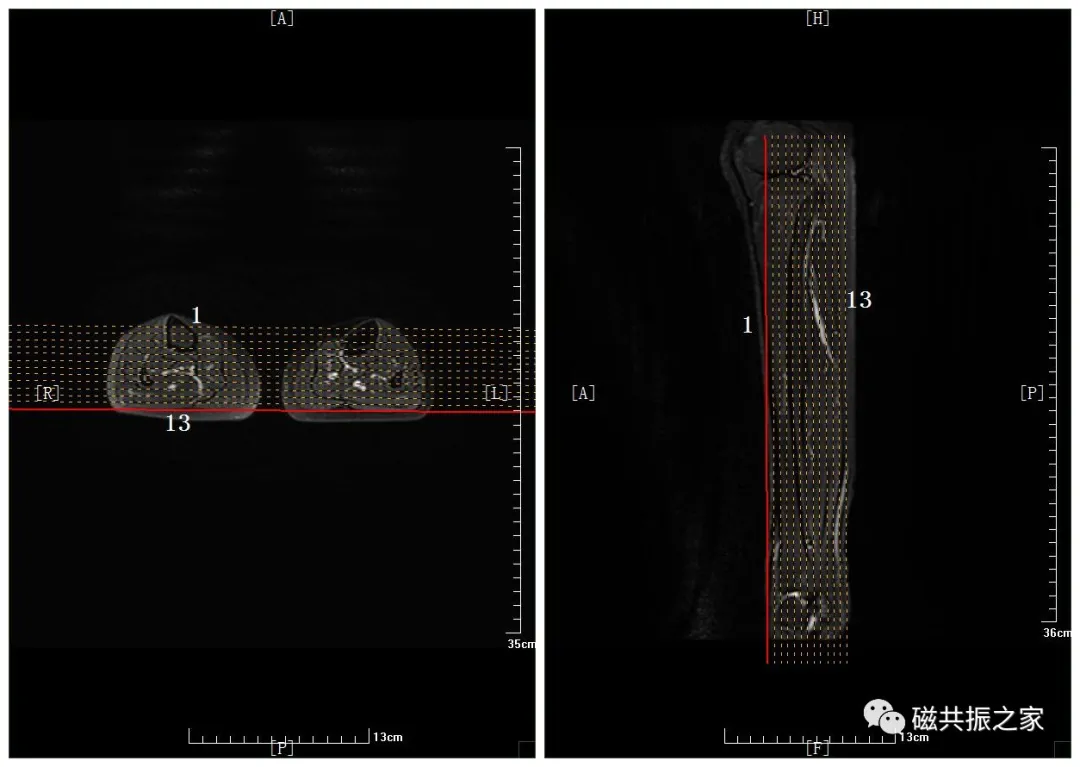

下面以双侧小腿扫描为例。

体位:仰卧位,足先进,身体与床体保持一致,遵循“三中心”原则(主磁场中心,线圈中心和扫描部位的中心尽量在一个点上)。如单侧扫描时,身体向健侧移动使扫描部位尽量靠近主磁场及线圈的中心。

常规扫描方位:横断位,冠状位,矢状位,“长轴+短轴”相结合的体位。

在横断位和矢状位上定位。在横轴位上调整定位线,双侧对称扫描;在矢状位上调整定位线使其平行于长骨长轴。两端尽量包全两端关节,如不能包含两侧,至少需包含临近患侧关节;需包括整个病变。